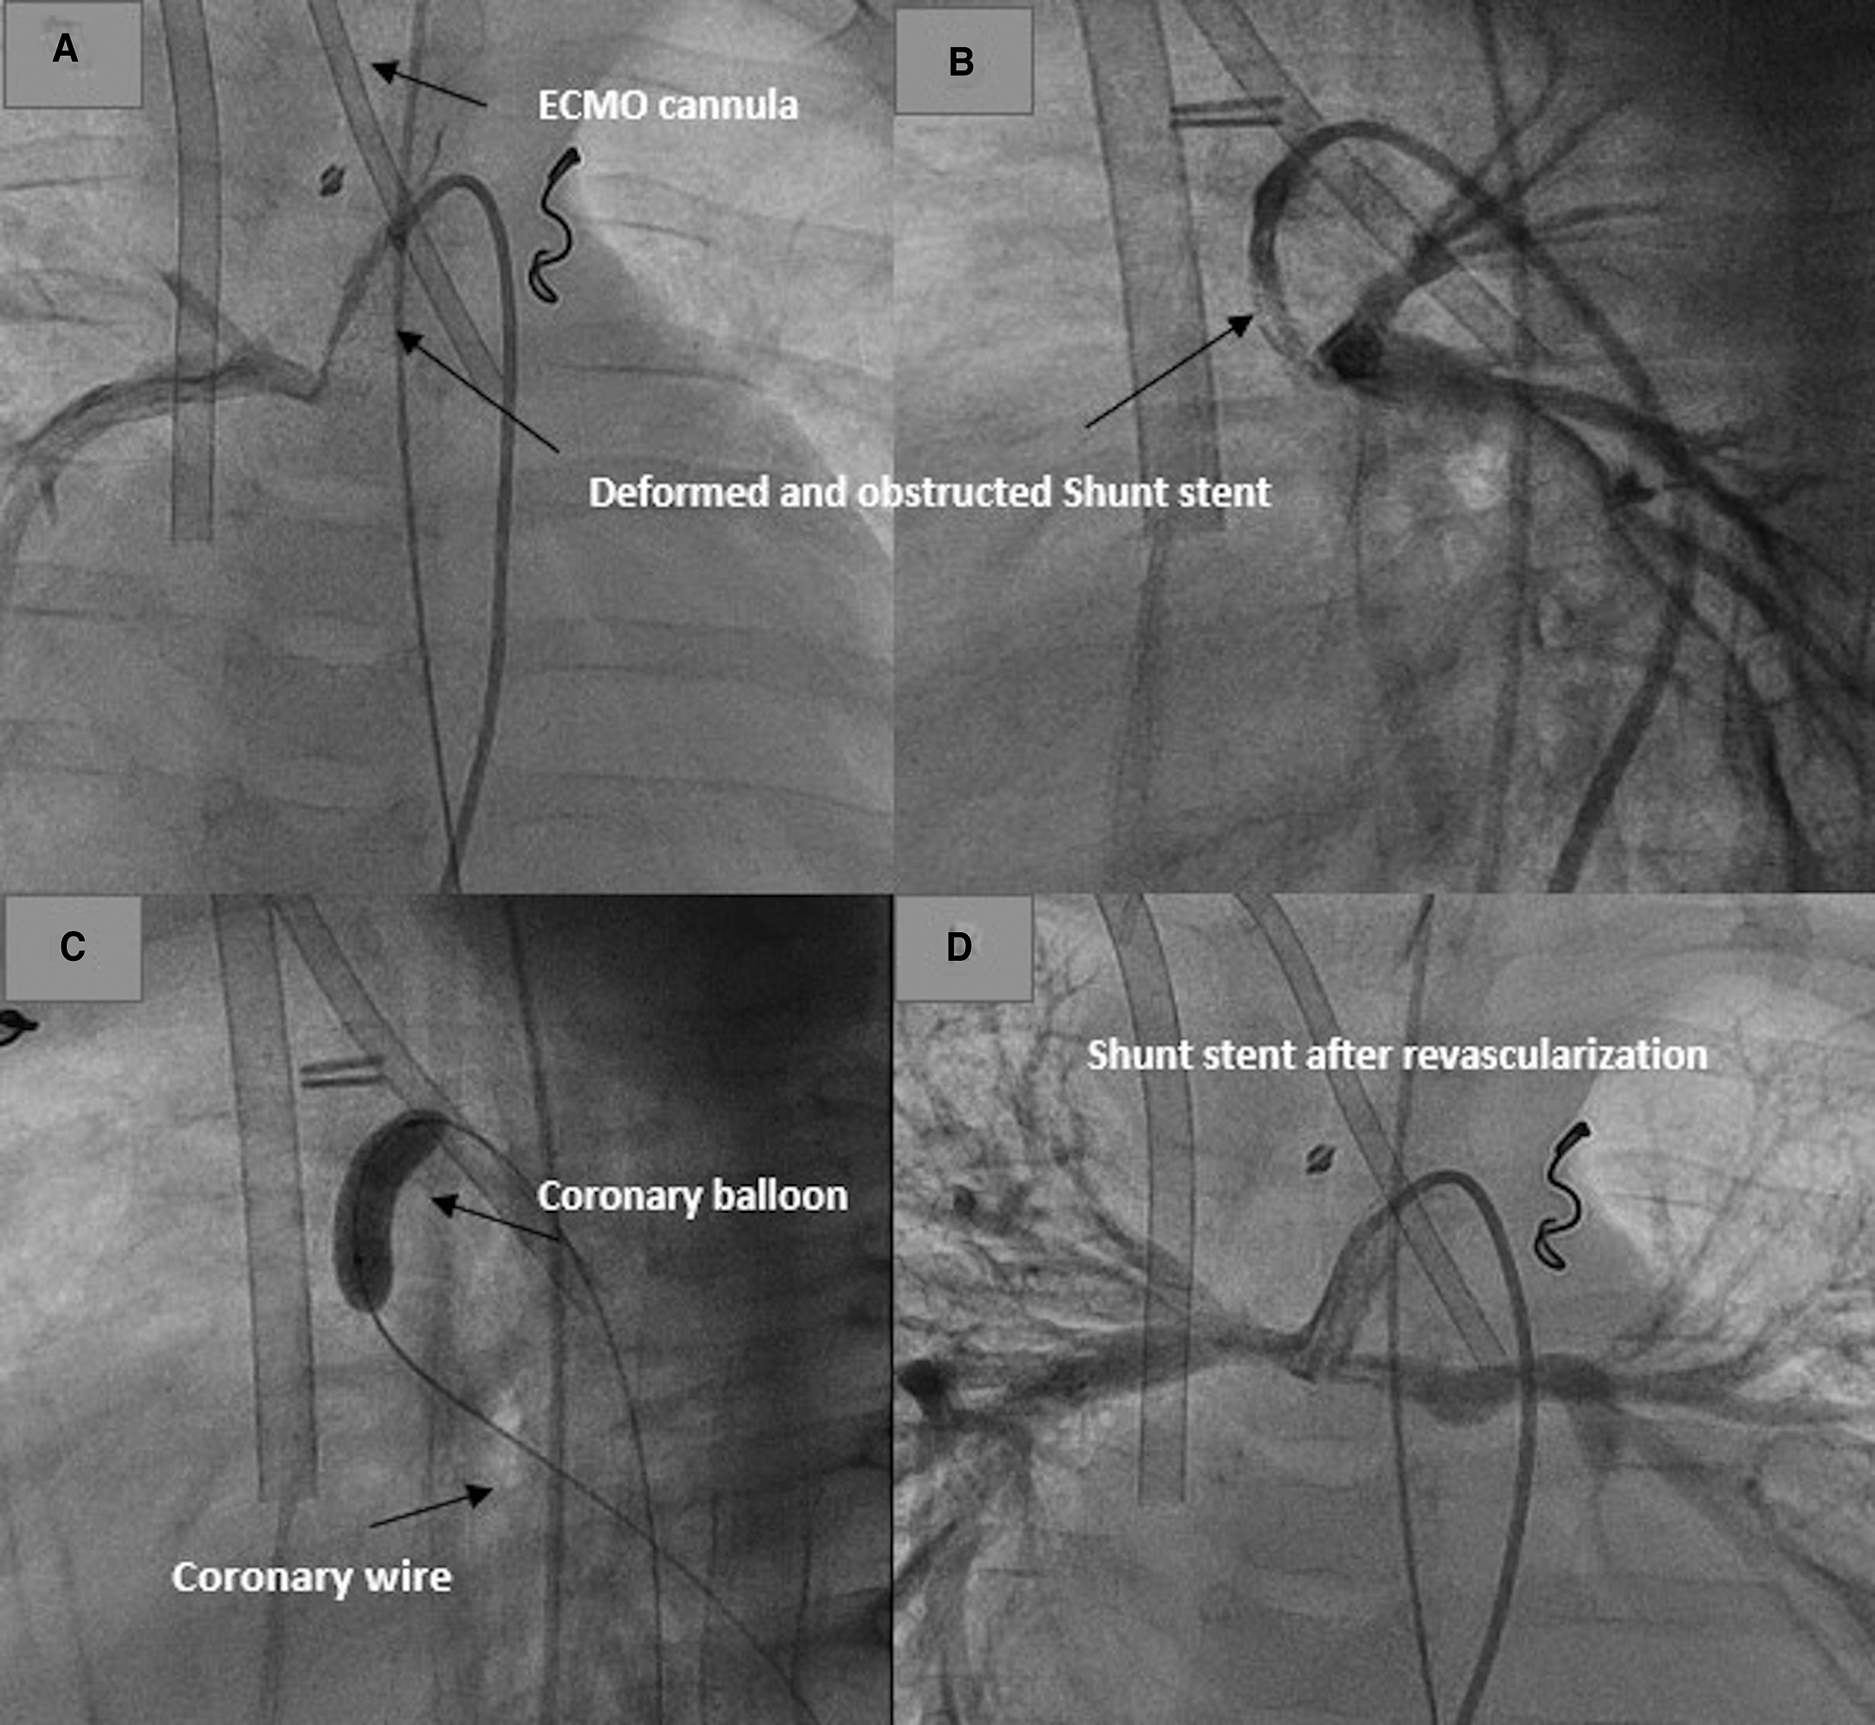

The first patient with HLHS needed a shunt stent due to shunt stenosis and underdevelopment of the right or the left branch pulmonary artery. He was referred to palliative therapy. Sixty days after the shunt stenting, he had to be resuscitated during his hospital stay due to hemodynamic deterioration after a crying attack. Burst massage during resuscitation led to stent deformation. The stent was completely compromised with no perfusion. The shunt revascularization was performed while the patient was on ECMO (Figure 4). The ECMO was decannulated 24 h after stenting.

Figure 4

Revascularization of a deformed shunt stent after resuscitation in a patient on ECMO. (A,B) Deformed stent in AP and lateral projections. (C) Recanalization and dilatation of the stent. (D) Shunt and pulmonary perfusion after shunt revascularization.